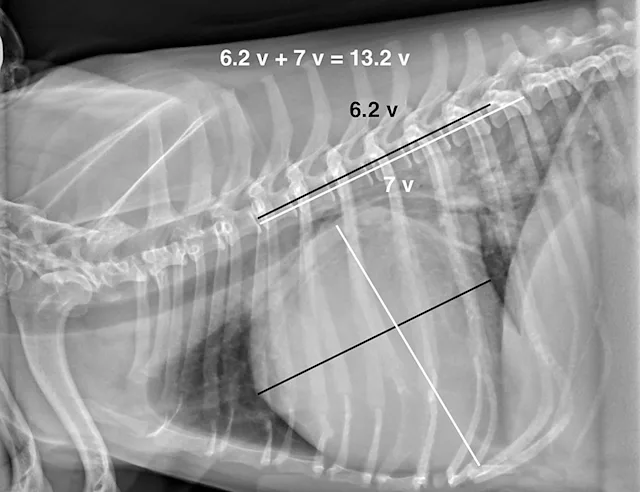

In dogs and cats, the vertebral heart score (VHS) system measures the width of the cardiac silhouette (ie, distance from cranial to caudal [ie, short axis] along the estimation of where the atria and ventricles meet) and from the carina of the trachea to the apex of the heart at its most ventral point (lines [ie, long axis] should be perpendicular to each other). These measurements are transferred caudally starting at T4 to calculate the VHS (Figure 4).2 Although this measurement is a good general guide, it can be overinterpreted, as cardiac chambers can change size without changing the shape of the cardiac silhouette.3

The average VHS in dogs is approximately 9.5 ± 0.5 with a normal range of 8.7 to 10.7. The measurement can change based on right or left recumbency (see a compilation of breed-specific VHS reference ranges available from Nguyenba in Suggested Reading). Measurements are more useful when diagnosing dilatative forms of cardiac disease and are reported to be less accurate in dogs with cardiac diseases with concentric hypertrophy.3 VHS for cats in right lateral recumbency is 7.3 ± 0.5.4 A VHS >7.9 has a high diagnostic accuracy in distinguishing cats with left-sided cardiac disorders from healthy cats.5

Because there are breed differences in VHS measurements, finding a reference range is valuable and can increase accuracy of the assessment.3,6 In a study, VHS measurements were found to be most accurate in Yorkshire terriers and Cavalier King Charles spaniels.3 Heart size relative to thoracic volume varies among dog breeds and is considered to be primarily due to thorax conformation. In barrel-chested breeds (eg, bulldogs, Boston terriers, Lhasa apsos), the cardiac:thoracic ratio is generally larger than in normal or deep-chested breeds. The VHS system was developed to help address this issue but its efficacy is unclear (see Benefits & Limitations of Vertebral Heart Scoring).7